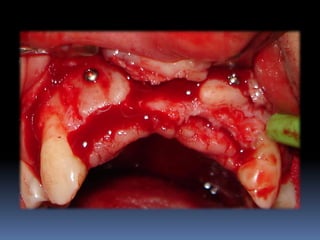

•Procedimentos de enxertia óssea para

restabelecimento de dimensões perdidas

•Compensações dos tecidos perdidos nas

próteses